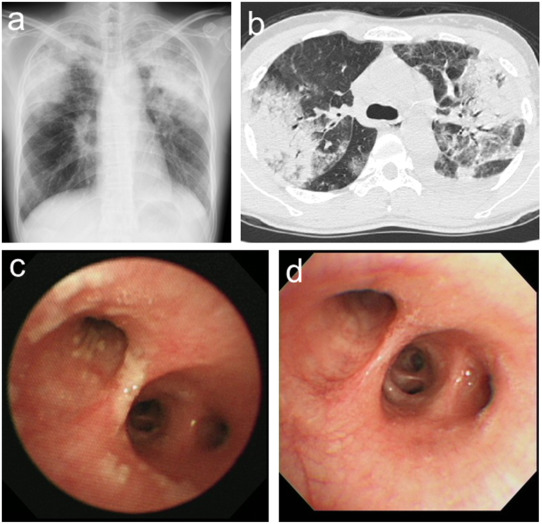

- Chest X-ray – A chest X-ray can show signs of lung inflammation, such as fluid accumulation or changes in lung tissue.

- CT scan – A more detailed imaging test that provides a clear picture of lung abnormalities.

- Bronchoscopy – In some cases, a doctor may perform a bronchoscopy to collect samples of lung tissue or fluid to examine under a microscope.